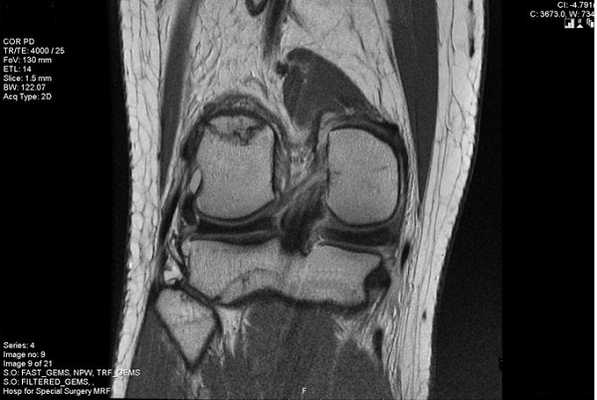

МР-изображение субхондрального перелома латерального мыщелка (зона повреждения указана стрелкой)

Протокол магнитно-резонансной томографии подытоживают заключением. В этом разделе документа интерпретируют патологические изменения, обнаруженные на срезах. Заключение МРТ коленного сустава может выглядеть так:

«На серии томограмм картина выявлена латеропозиция надколенника, повреждения медиального удерживателя и хондромаляция хряща последнего. Умеренный посттравматический отек тела Гоффа. Экссудативный синовит. Бурсит инфрапателлярной сумки. Умеренный отек мягких тканей в подколенной области».

В заключении МРТ обозначают суть и распространенность патологических процессов. При выдаче результатов рентгенолог может кратко пояснить медицинские термины и порекомендовать пациенту, к какому врачу обратиться.